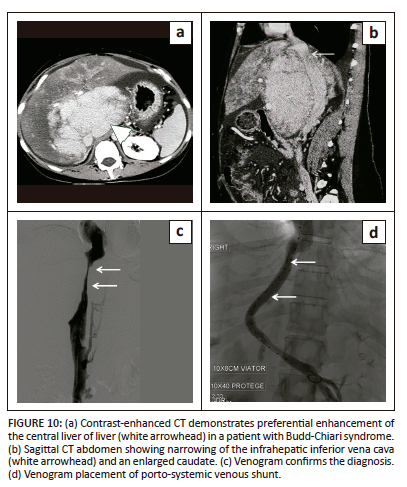

Budd-Chiari syndrome results from obstruction of the hepatic vein outflow tract. Budd-Chiari syndrome is most commonly associated with a hypercoagulable state. Uncommonly congenital web, stenosis or tumour can result in obstruction of the hepatic segment of the IVC. Inferior vena cava compression and narrowing by a massively enlarged caudate lobe is another uncommon cause.1 The caudate lobe undergoes hypertrophy in most of the cases and is relatively spared of the effects of Budd-Chiari as it drains directly into the IVC. However, caudate lobe hypertrophy is a non-specific finding. On the other hand, a prominent caudate lobe vein measuring more than 2 mm is a specific sign seen in half of the patients with Budd-Chiari syndrome.3

In the acute phase, arterial phase imaging demonstrates preferential enhancement of the central region of the liver, which includes the hypertrophied caudate lobe and part of the left lobe with washout of contrast in the central region and accumulation of contrast peripherally in the portal venous phase (flip-flop pattern of enhancement) (Figure 10).3

In chronic Budd-Chiari syndrome, the imaging appearance depends on the contrast phase and regenerative nodules. Regenerative nodules may be seen as hyperattenuating lesions with hypervascular enhancement in the arterial phase but most are difficult to identify on imaging because of their small size. On MRI, regenerative nodules have variable signal on T1-weighted images, are iso-hypointense on T2-weighted images, and do not enhance in the arterial phase. On the contrary, HCC shows heterogeneous enhancement on the arterial phase, are encapsulated and invade the portal and hepatic veins.1,3 Benign nodules are hyperintense to normal liver on post-contrast delayed imaging with hepatocyte-specific phase agents such as gadobenate compared with HCC.3 Azygos, hemiazygos, and lumbar veins bypass the occluded IVC segment via collaterals.1 Extrahepatic collaterals may be seen in Budd-Chiari as well as other IVC syndromes because of hepatic outflow obstruction but the presence of intrahepatic collaterals is highly suggestive of Budd-Chiari.30